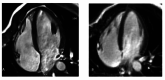

Figure 1. CT lung

CT lung showing right-sided pneumonia and right-sided pleural effusion CT: computed tomography